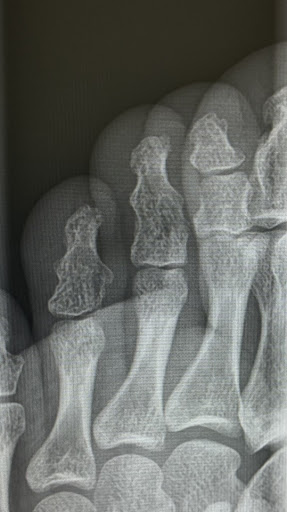

足の中指を骨折し、1日でも早く走れるようになりたくて来院しました。

こちらでは骨の癒着を早める治療器があり、しかも保険適用になるので可能な限り毎日通いつめて約2週間後のレントゲンが2枚目になります。

治療経過はかなり良好だと思います。

また、初診時に歩き方のコツやテーピングのコツなど、病院ではあまりしっかり教えてもらえなかったところまで詳しく話してくださったおかげで“うっかりやってしまわない方がいい動き”も最小限にできていると思います。

このまま1日も早い完治を目指して、しっかり通おうと思います。